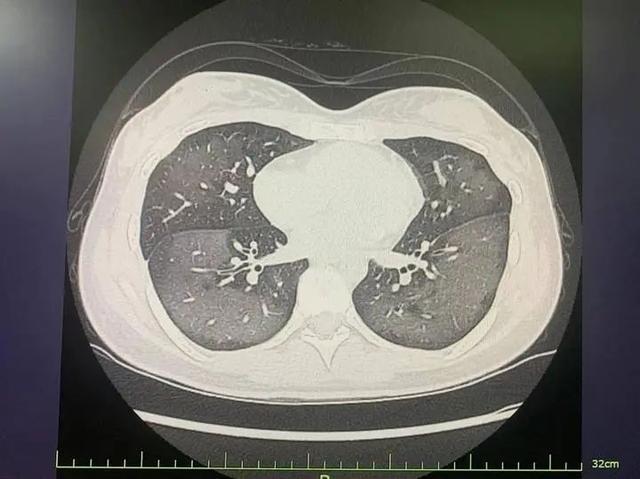

- 危重期:即使吸氧仍呼吸困难,影像学显示白肺

- 高分辨率CT:早期发现毛玻璃样改变